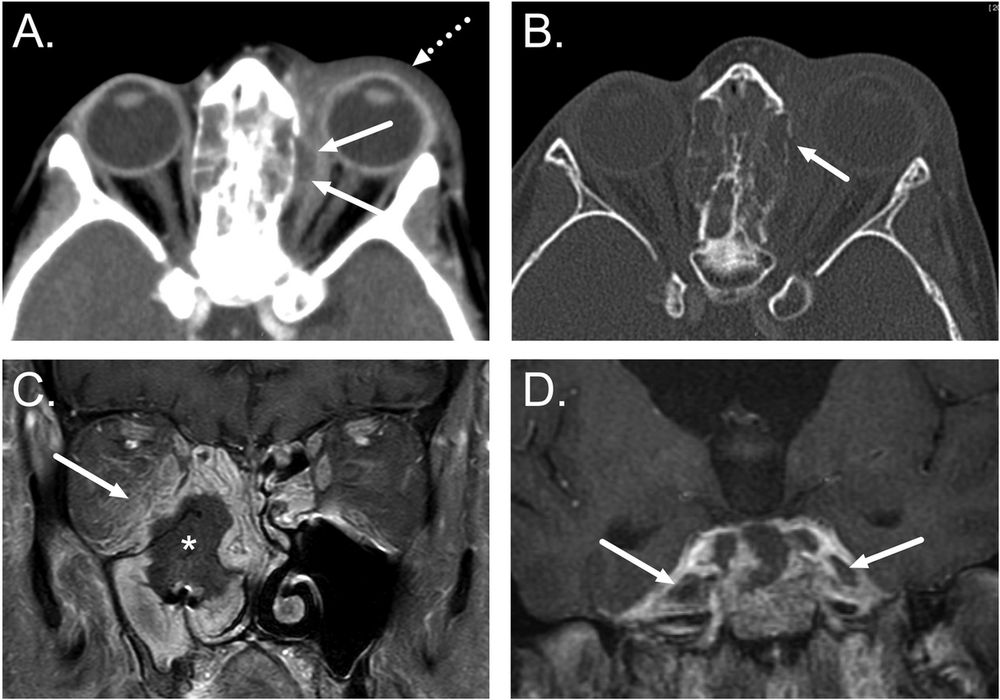

Acute head and neck infections are common in the population and can have serious complications. This #ESREssentials paper gives new practice recommendations by the European Society of Head and Neck Radiology (Jussi Hirvonen et al.)

ESR Essentials: acute infections of the head and neck—practice recommendations by the European Society of Head and Neck Radiology - European Radiology

Abstract Acute head and neck infections are common in the population and can have serious complications. Prompt diagnosis and treatment are necessary to avoid morbidity and mortality. Imaging is not…